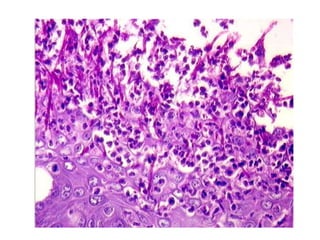

CASE 8 • A70-year-old male • C/O- Bad breath and pus discharge from upper left region of jaw since one month. • K/C/O - Diabetes mellitus • Three months came to Emergency Department in an unconscious state- Diabetic ketoacidosis with renal failure

• #57 Showing fungal hyphae (H&E, ×40) Histology of the received specimen showed stratiÞ ed squamous epithelium which was ulcerated with intraepithelial split formation; underlying connective tissue showed numerous minor salivary glands, ducts and muscle tissue. Large amounts of necrotic tissue were evident with cellular degeneration and debris [Figure 4]. Fungal hyphae were seen with neutrophil inÞ ltration and generalized chronic inß ammatory cell inÞ ltrate within connective tissue. Hyphae were aseptate, branched and resembled mucormycosis. Areas of hemorrhage were present

• #58 Hemotoxylin and Eosin stain histopathology showing necrotic and edematous tissue with neutrophilic infiltrate and hyphae.

• #59 Grocott-Gomori methenamine-silver (GMS) stain highlighting fungal elements.